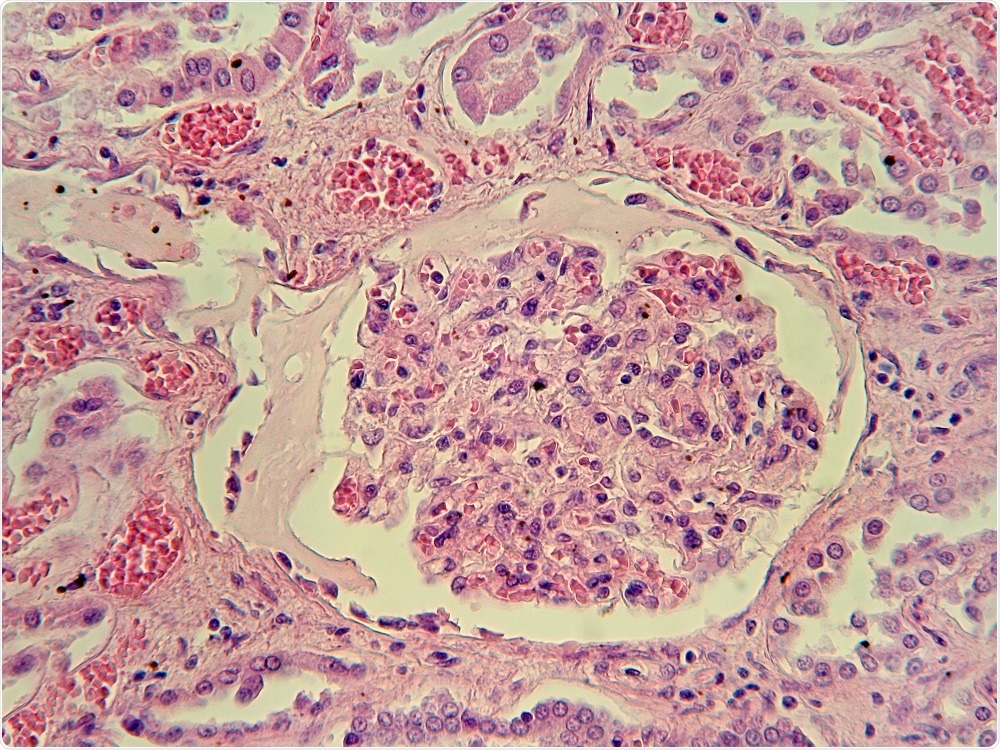

Credit: Jubal Harshaw/Shutterstock.com

Alport Syndrome is a hereditary kidney disease that affects the glomerular basement membrane within the filtration system of the kidney. This allows blood and proteins to escape into the urine and ultimately leads to end-stage kidney disease and hearing loss.